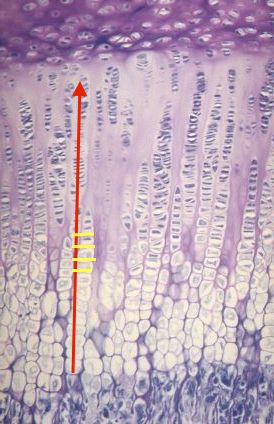

Regarde cette image :

cartilage de conjugaison métaphysaire.jpg

Les cloisons horizontales sont en jaune, tu dois les casser pour permettre la croissance axial en rouge :jump: